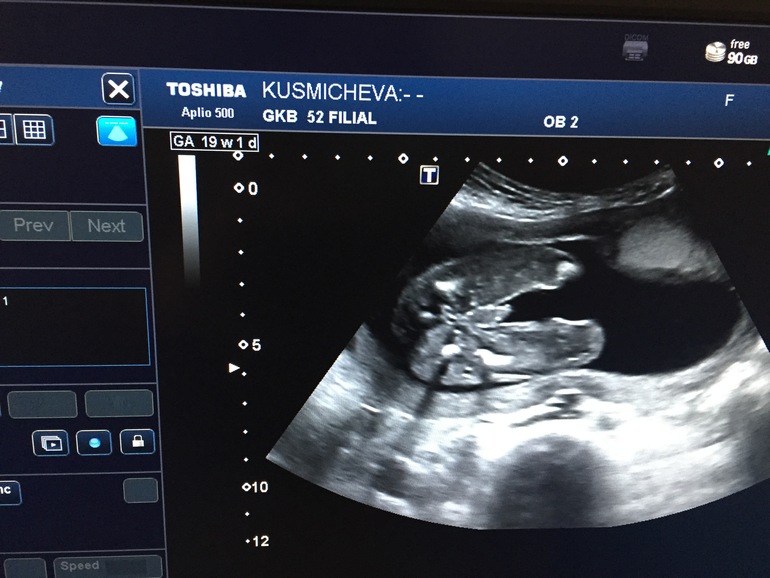

Ничегошеньки не могу понять. Вроде на мальчишку не похоже, но что-то смущает. Хотя мальчик на узи немного по другому выглядит. Вот мой самый младшенький в животике (узи делали 4 дня назад)